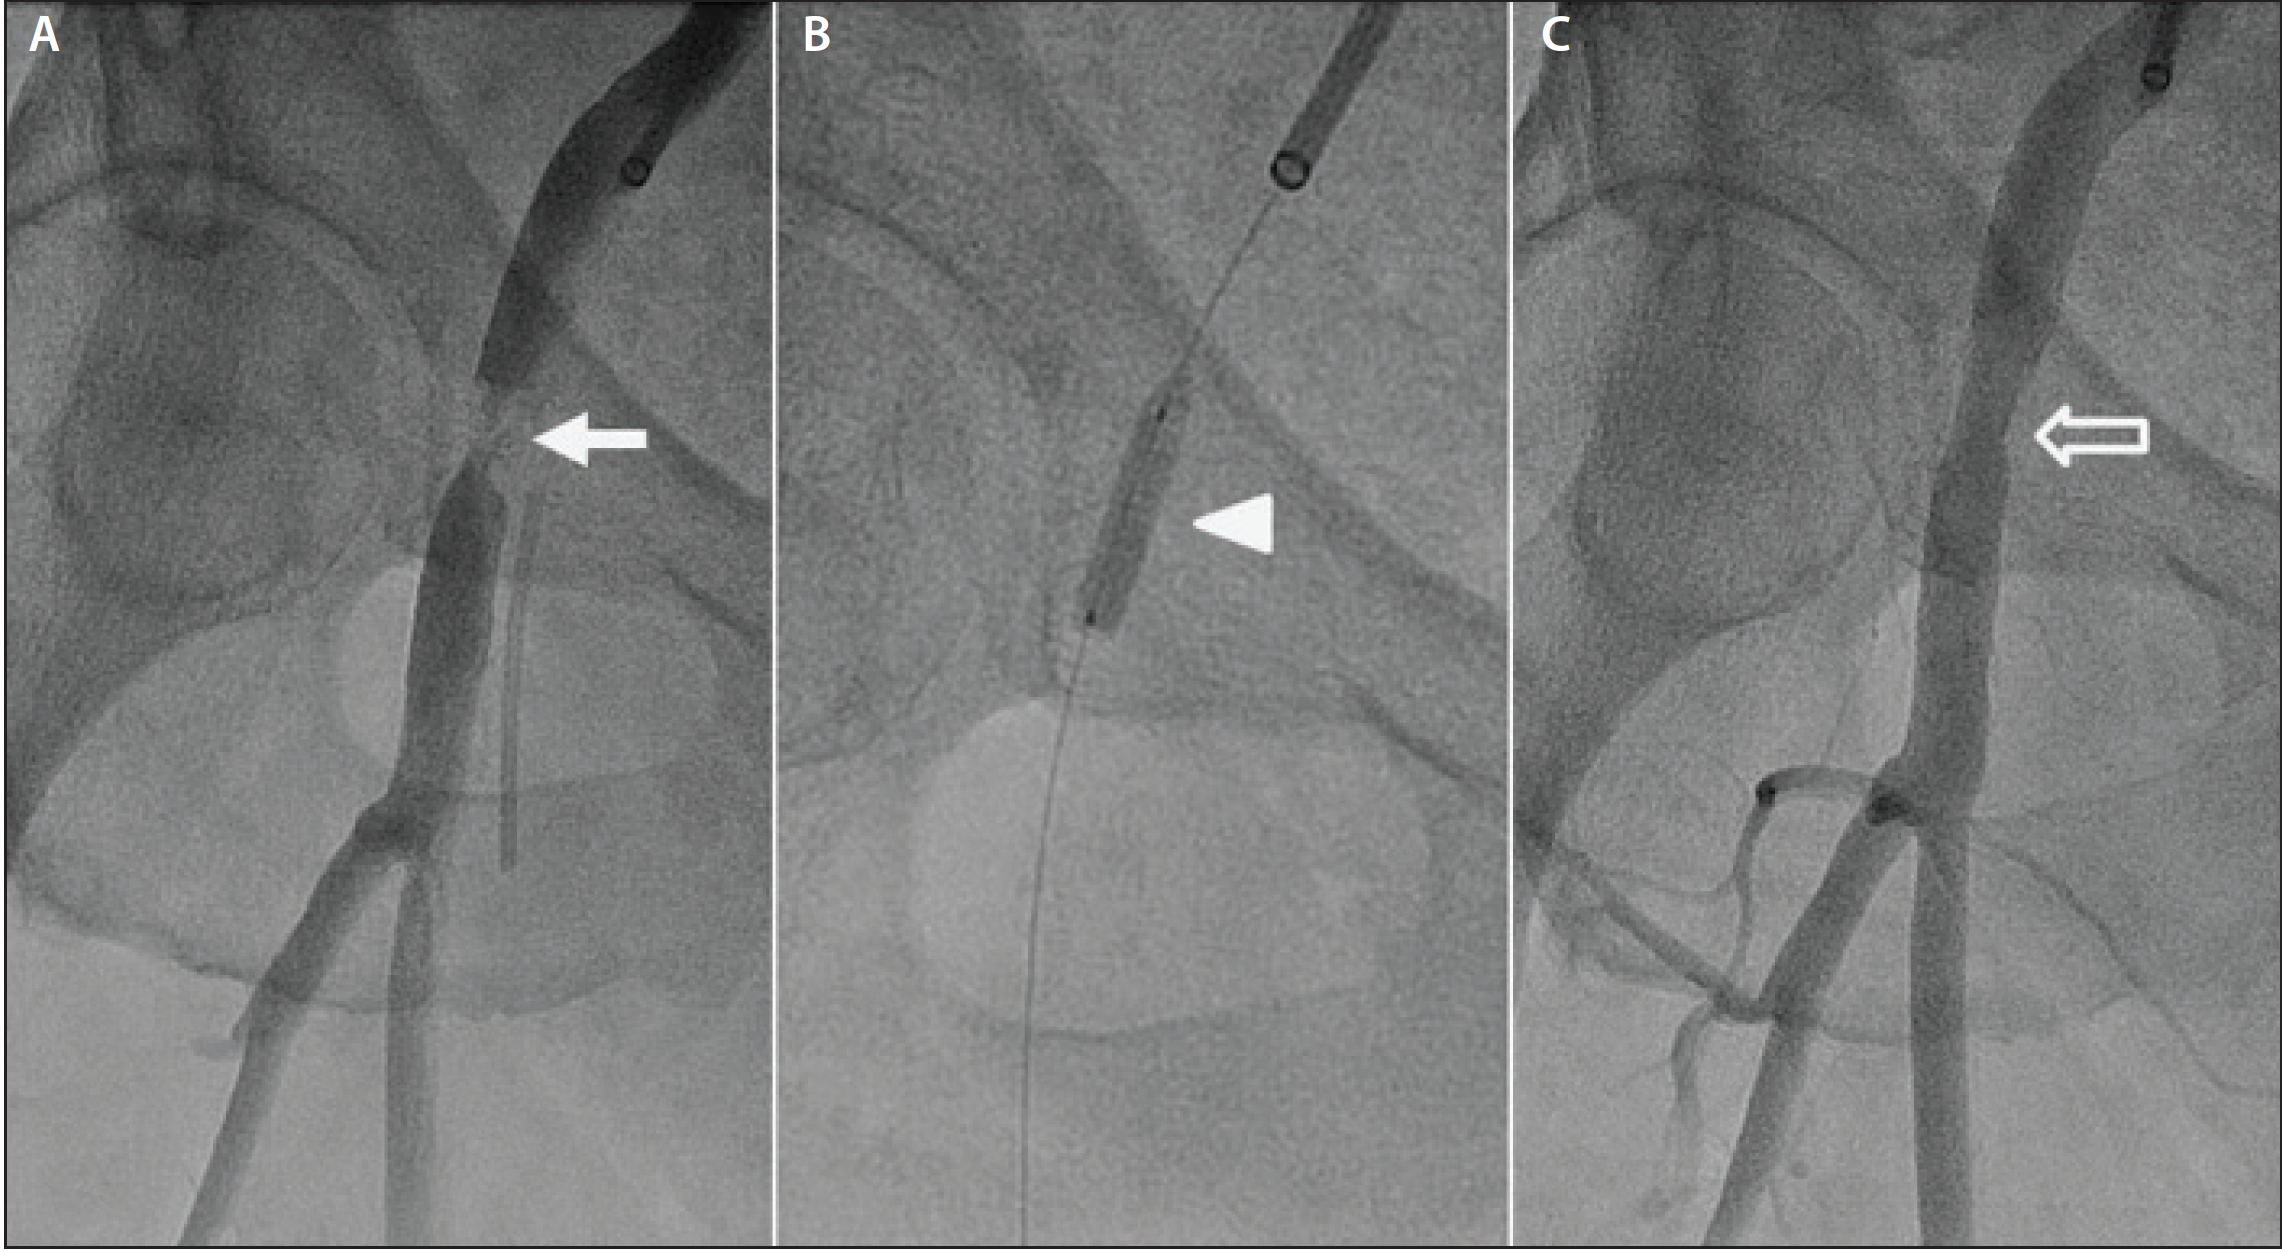

Figure 3. Failed preclosure with reinsertion of a 14-F sheath through the arteriotomy site (hollow arrow) for temporary hemostasis (A). Crossover catheter (arrow) from the contralateral iliofemoral artery used to perform selective angiography to locate the arteriotomy site and localize the SFA and deep femoral artery bifurcation (arrowhead). Positioning of a Viabahn 10- X 50-mm ePTFE-covered nitinol self-expanding stent (arrow) across the arteriotomy site (hollow arrow) over a 0.035-inch Supra Core guidewire (Abbott Vascular) (B). The device is positioned above the SFA and deep femoral artery bifurcation (arrowhead). Successful deployment of an ePTFE-covered nitinol self-expanding stent (arrow) in the right common femoral artery with complete obliteration of flow through the arteriotomy site (C). The stent graft is deployed above the SFA and deep femoral artery bifurcation (arrowhead).

In significant bleeding complications secondary to preclosure failure, exclusion of the arteriotomy site with the deployment of an ePTFE-covered stent across it has been our de facto management strategy. This is the quickest and most efficacious approach when utilizing percutaneous endovascular therapy as the first-line treatment. After achieving temporary hemostasis, crossover access from the contralateral iliofemoral artery is immediately gained. This allows selective angiography of the right iliofemoral artery to localize the arteriotomy site and, more importantly, to pinpoint the superficial femoral artery (SFA) and deep femoral artery (profunda femoris) bifurcation (Figure 3A).

Angiography should be performed 30° to 40° ipsilateral to the access site in order to best visualize the bifurcation. In the deployment of the ePTFE-covered stent, one would place the device above the bifurcation, so as not to compromise blood flow to one of the bifurcating vessels. A 0.035-inch stiff guidewire is advanced across the arteriotomy site and positioned as distally in the distal SFA or popliteal artery segment as possible to provide the most support during delivery of the bulky ePTFE-covered stent graft. Figure 3B illustrates the positioning of the ePTFE-covered nitinol self-expanding stent across the arteriotomy site. Removal of the large-bore sheath is followed by immediate deployment of the ePTFE-covered nitinol self-expanding stent. Prior to withdrawal of the large-bore sheath, the guidewire of the former sheath is exchanged for a 0.035-inch stiff Glidewire (Terumo Interventional Systems). The Glidewire is left in situ during the removal of the large-bore sheath, and the stent graft is deployed over the guidewire. The latter is only pulled out when hemostasis is achieved with the deployment of the ePTFE-covered nitinol self-expanding stent, as shown in Figure 3C. With regard to the diameter size of the implanted stent graft, the device should be oversized by 20% relative to the diameter of the vessel.